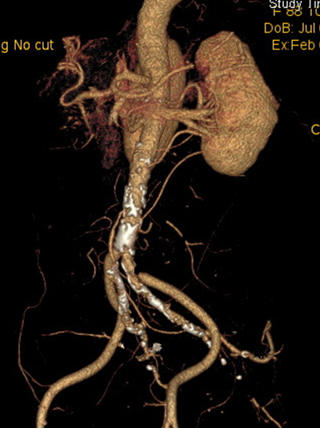

病例2:腹腔镜联合开腹治疗

患者女性,88 岁 7 月,因 "腹痛 30 小时" 入院,既往房颤病史多年。查体示脐周、左下腹局限压痛、反跳痛,腹腔镜探查发现可疑肠道缺血坏死,遂中转开腹行肠系膜动脉切开取栓+坏死肠道切除术,术后复查 DSA 显示血管通畅,患者顺利康复。

图:术前影像